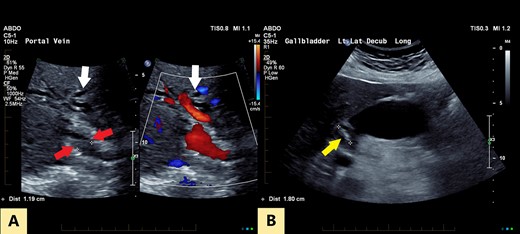

MIP reconstruction of 3D MRCP reveals abrupt segmental stricture of the common hepatic duct with marked intrahepatic biliary dilation. Trifurcation of the biliary confluence into the left hepatic duct, aberrant segment 6 duct and the right hepatic duct. The right hepatic duct is formed by the union of right anterior (segment 5,8) duct and segment 7 duct while the segment 6 duct is joining separately at the confluence. The approximate plane of surgical resection is indicated.

The patient underwent an open pancreaticoduodenectomy and cholecystectomy. Surgical resection was extended proximally to include the biliary confluence and biliary transection was performed to reveal four separate bile duct openings consisting of the right anterior and posterior sectoral ducts, a separate segment 6 duct and the left hepatic duct (Fig. 4).